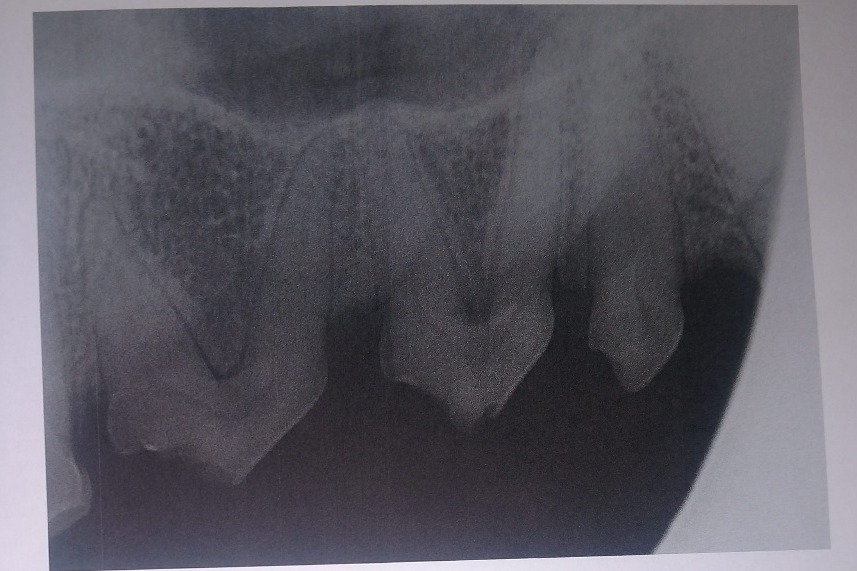

The radiographs laid out a dim story of that long term damage: all 4 canine teeth were dead, 2 of those canines were broken off from the recent attempt on the gate; all of her lower incisors, and several molars on each side were also dead. The vet was surprised, in spite of massively evident wear and tear, that her upper incisors appeared to still be alive. More of her teeth were dead than live. However, there was some good news in that her gums were completely free of gum disease, she had very little plaque and tartar buildup, and that she hadn't lost any of the bone her teeth were seated in.

The following photos are her radiographs for anyone that knows how to read them, so you can see all the dead teeth that need future extractions, and some show the root canals: